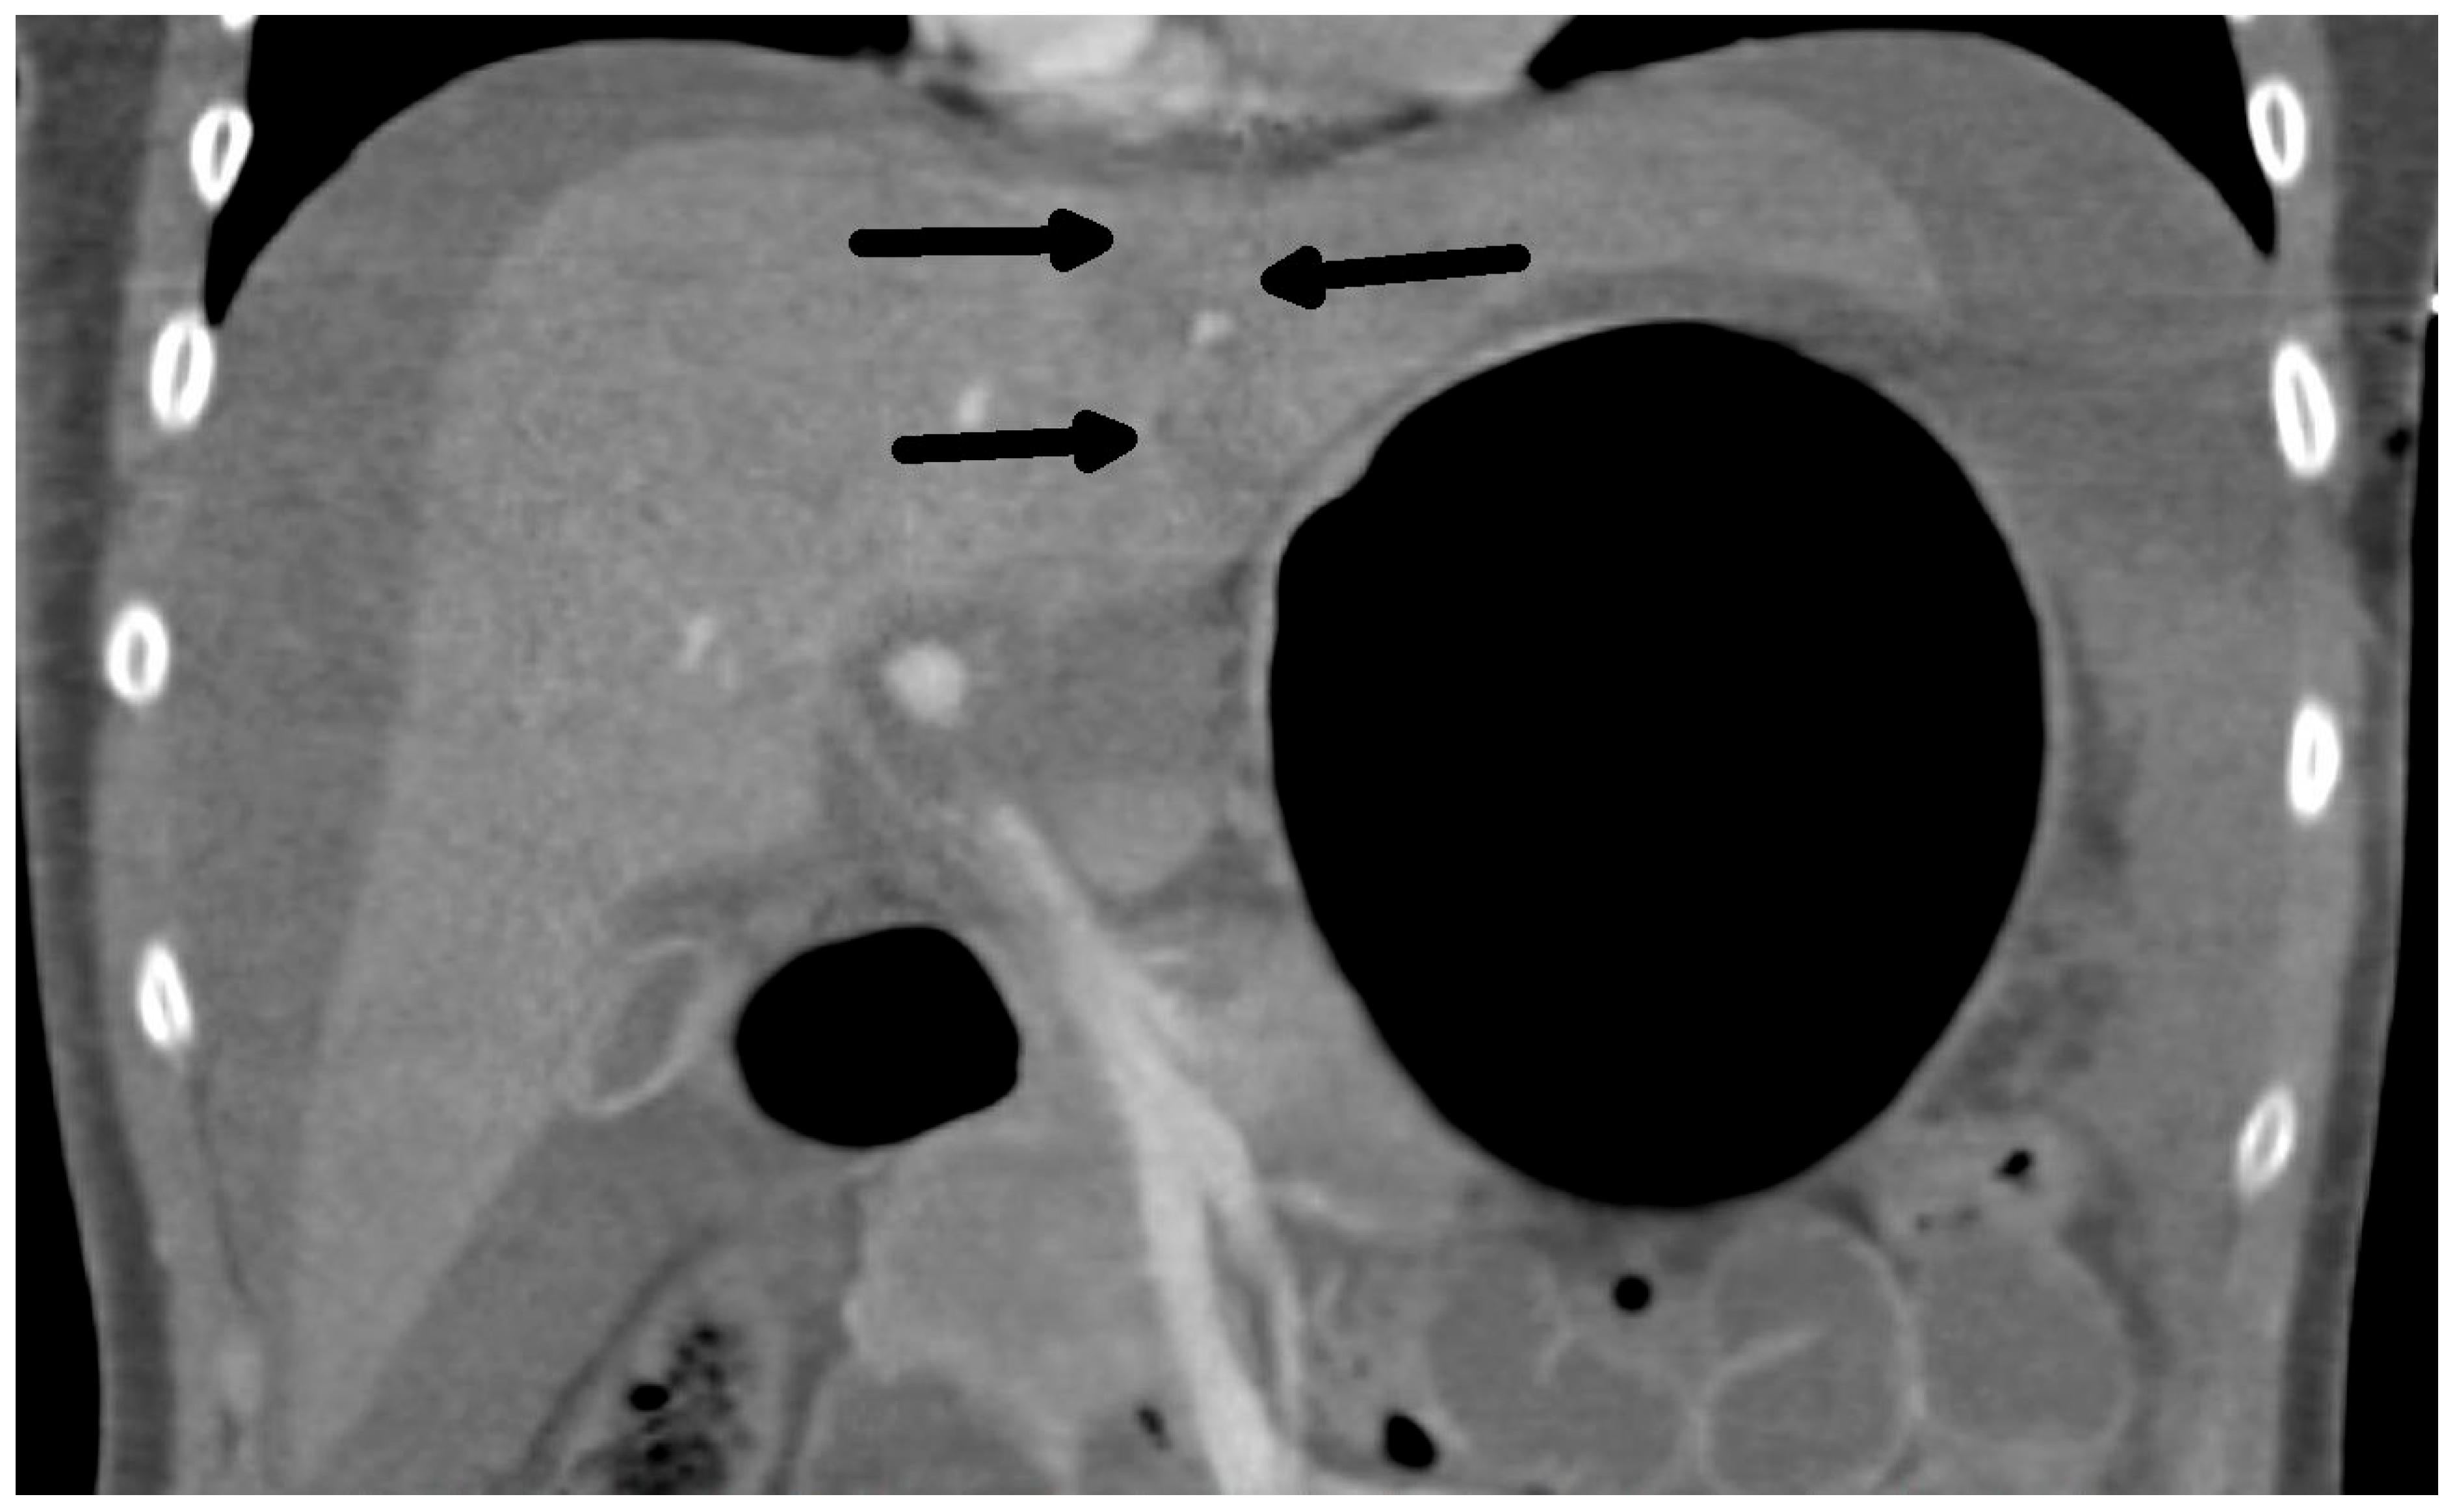

The diagnosis of liver injury was made by clinical and paraclinical examination and confirmed by imaging techniques. (computed tomography (CT) or ultrasound) (Table 2) (Figure 1 and Figure 2).

Figure 2.

CT scan: Rupture of the liver along falciform ligament (arrows) and hemoperitoneum frontal view.